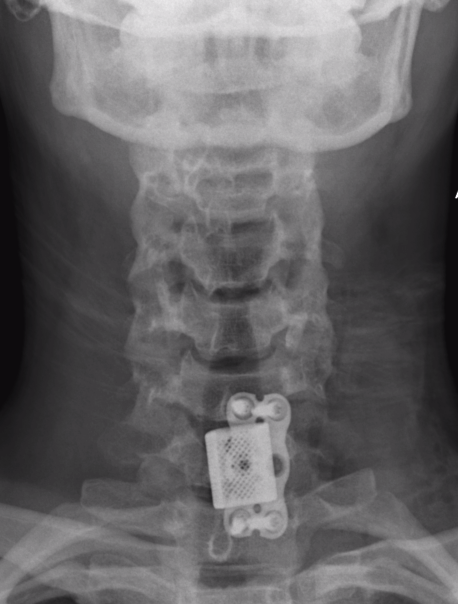

X-ray

AP

- widening between pedicles is hallmark on AP

A. Anterior corpectomy & fusion with tricortical graft + plate

B. Anterior corpectomy & fusion with mesh cage + bone graft + plate

+/- Supplemental posterior fixation / cervical lateral mass screws

Anterior corpectomy and tricortical graft